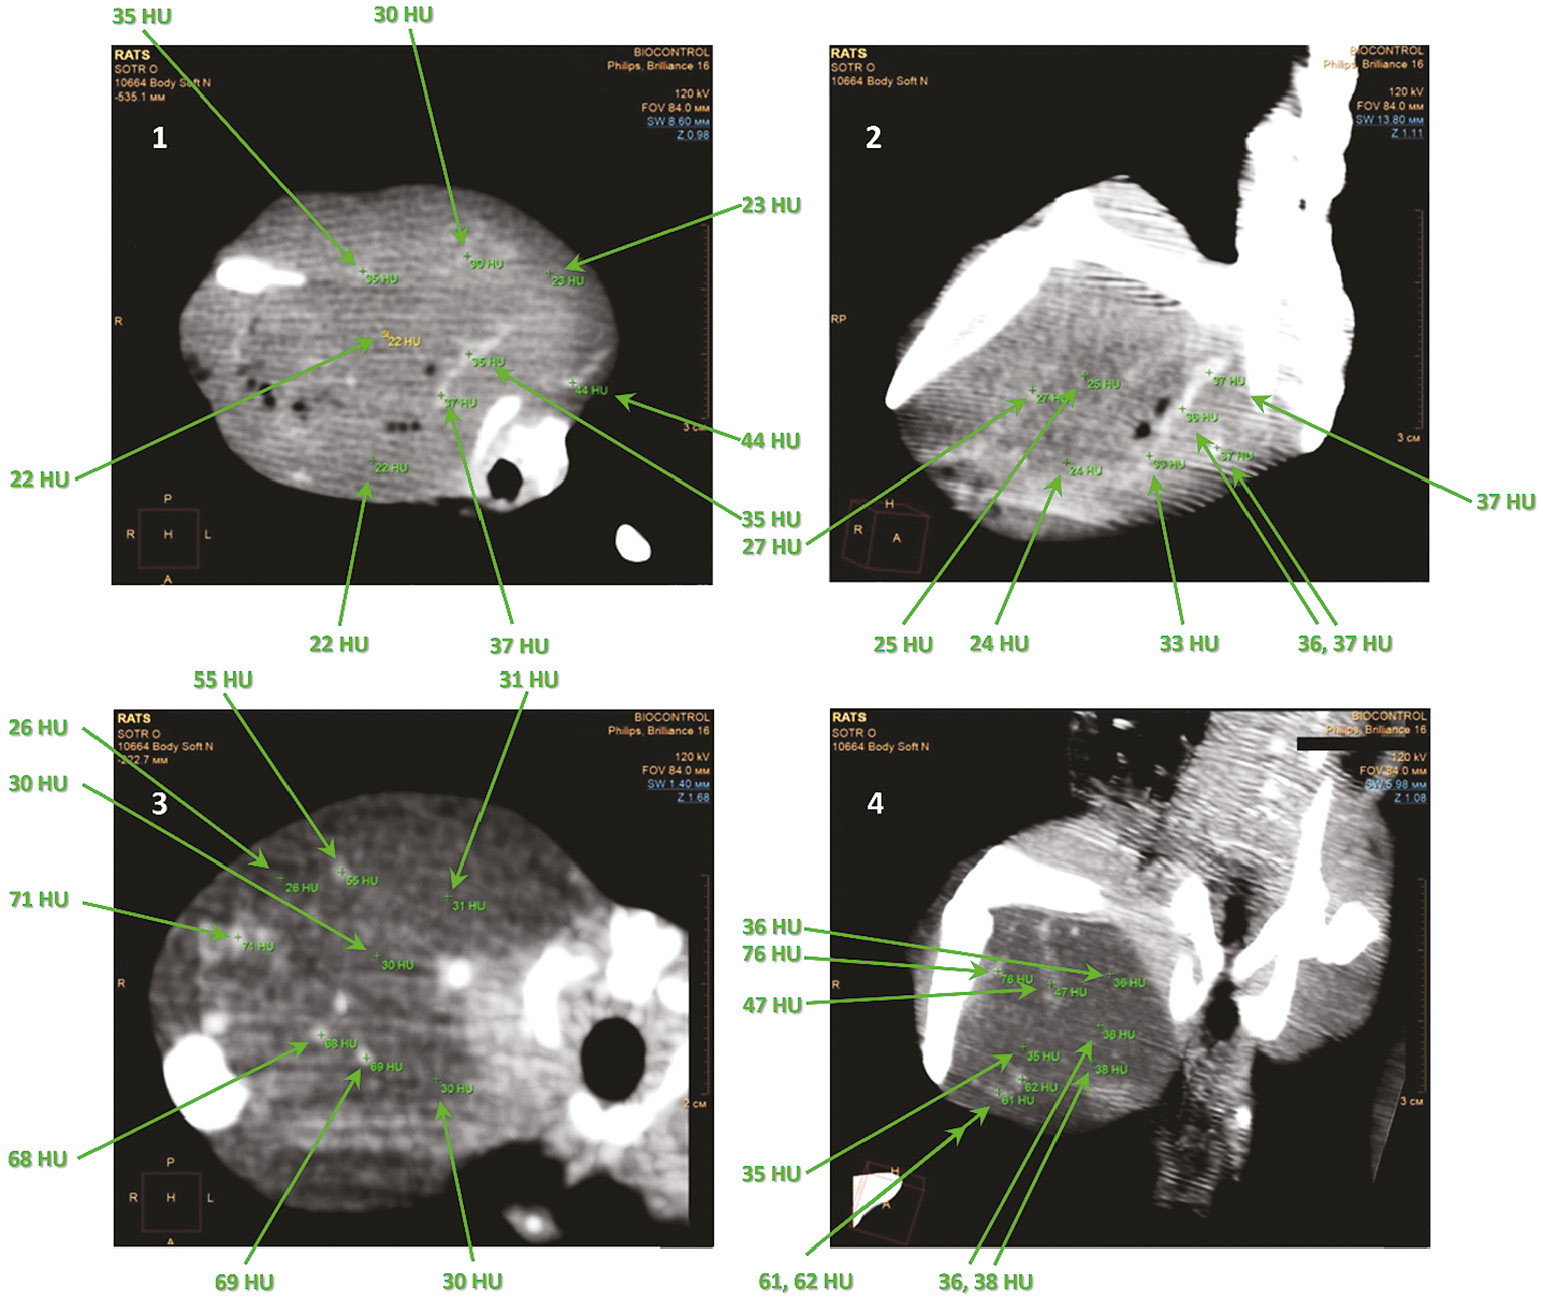

КТ-исследование и рентгенография при применении наносистем

Исследование in vitro показало выраженное контрастирование. Плотность препарата составила от –54 до –120 единиц по шкале Хаунсфилда (HU), что соответствует плотности жировой/соединительной ткани. Изучение in vivo в диапазоне доз показало не зависящее от дозы выраженное контрастирование сосудистого русла опухоли. Плотность сосудов опухоли составила от –47 до –80 HU при плотности ткани опухоли от –24 до –26 HU. МНЧ показали выраженные и стойкие контрастирующие способности по результатам КТ-исследования. Контрастирование сосудов, выявленное через 30 мин после в/а введения, сохранялось в течение 14 дней наблюдения. Длительное сохранение контрастирующего эффекта при КТ-исследовании свидетельствует о стабилизации наносистем или МНЧ в сосудах опухоли (рис. 4), тогда как метод рентгенографии (рис. 5) не позволяет детектировать частицы.

Рис. 4. КТ-исследование опухолевого узла под двумя разными углами (в поперечной и сагиттальной плоскостях) в бедренной мышце крысы через 30 мин (1, 2) и 14 дней (3, 4) после введения наносистем на основе магнитных наночастиц и человеческого сывороточного альбумина (в количестве 60 мкг по магнитным наночастицам).

Fig. 4. CT imaging of the tumor node from two different angles (transverse and sagittal planes) in the rat femoral muscle after 30 minutes (1, 2) and 14 days (3, 4) after the injection of nanosystems based on magnetic nanoparticles and human serum albumin (corresponding to 60 μg magnetic nanoparticles).